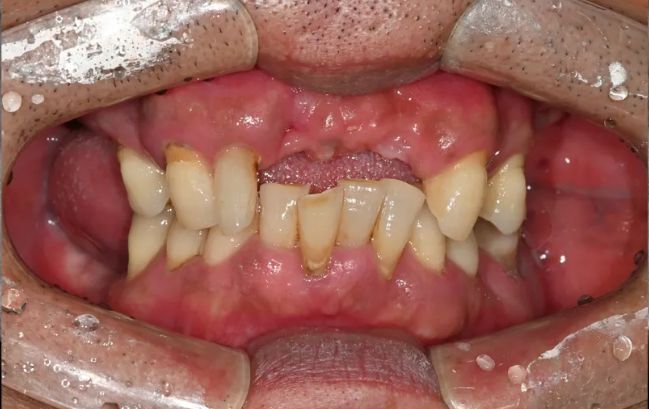

2021-09-06

2022-03-0560대 남성, 수면 전체 임플란트 13개 식립